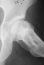

At 28 years of age, he had been having increasing pain in his right hip. He had a limp when he was tired. Positive Trendelenburg's sign was observed on the right. Internal rotation was limited to 25 degrees. All other motions were normal. X-ray showed cystic change. At the 29 years of age, he underwent bone graft of the right femoral head for degenerative cyst. At 35 years of age, only internal rotation was limited to 20 degrees. He still had pain in his hip that relates primarily to weather or to excessive walking. Only internal rotation was limited to 20 degrees. He had hip pain at the extremes of flexion and internal rotation. X-ray showed the progression of the cystic change. CT which was performed because of the question of loose bodies in the hip did not seem likely that the densities were actually in the hip joint. The antero-medial location of the cysts facing the anterior margin of the acetabulum was well depicted in CT.

28 yrs, 29 yrs, 30 yrs, 35 yrs .